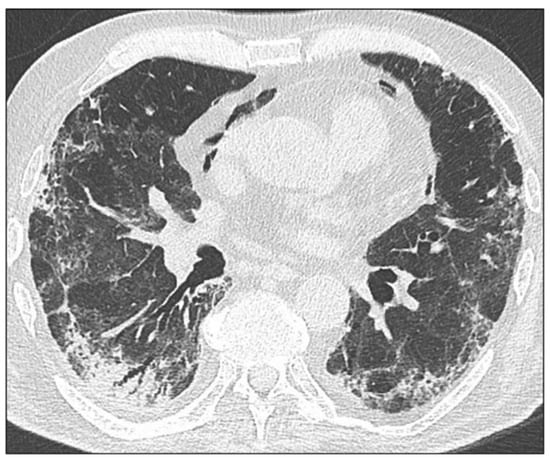

3.1.1. Ground Glass Opacities

3.1.3. Linear Bands

3.1.4. Reticulations

3.1.5. Bronchiectasis/Bronchiolectasis

3.1.6. Loss of Pulmonary Volume